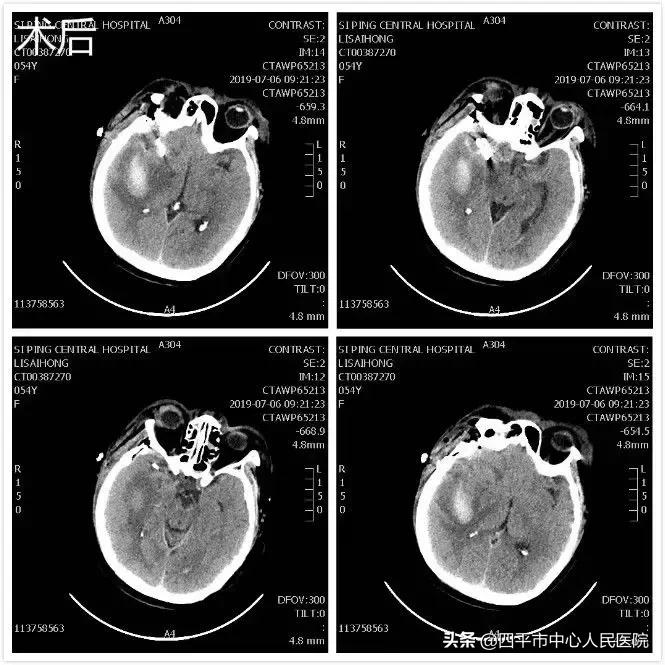

Case 6 前交通动脉瘤夹闭术后

患者张XX,入院前2天活动过程中无明显诱因出现头颈部疼痛,无恶心、呕吐,无发热,当时患者神清语明,自行走到我市某院检查头部CT后,诊断为蛛网膜下腔出血,进一步DSA检查提示:前交通动脉动脉瘤、左侧颈内动脉闭塞。当时,该院建议或者到长春治疗,或者请教授到该院手术治疗。经家属协商后决定在贵院请陆军总医院教授行大脑开颅前交通动脉瘤夹闭术,由于术后昏迷不清,躁动,发热,于术后第2天转到我院系统规范治疗,病程中患者出现肺炎,脑血管痉挛,脑积水。脑血管痉挛经治疗改善,脑积水行脑室腹腔分流手术,现患者神志清楚,运动性失语,可配合指令动作,四肢可动。